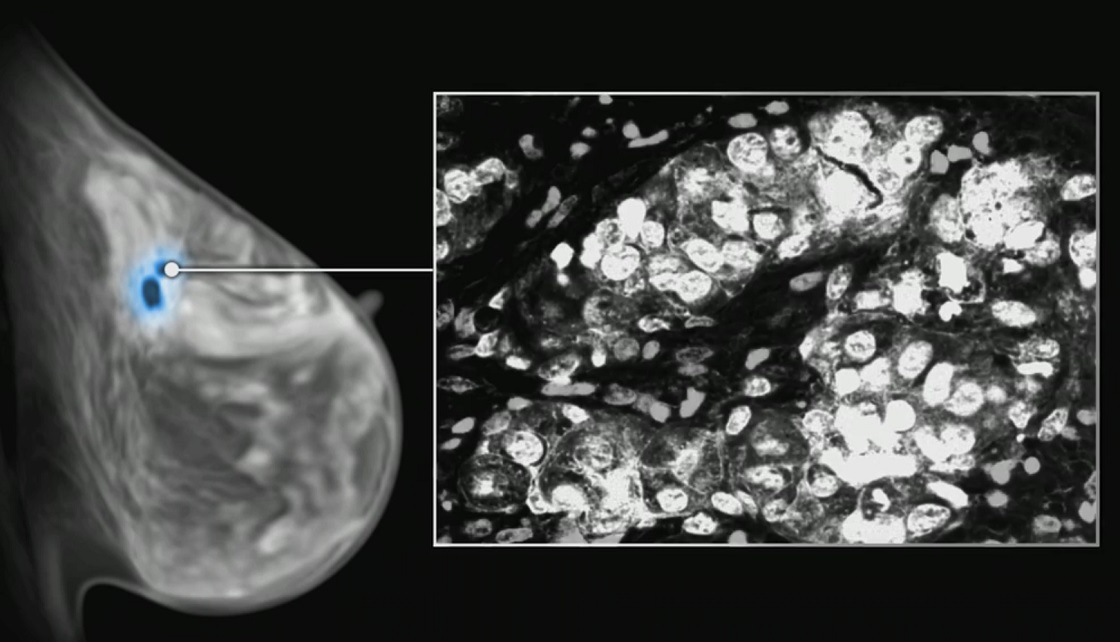

PROTEJAREA SĂNĂTĂȚII PACIENȚILOR ONCOLOGICI ÎN PANDEMIA COVID-19

”Și un deces prin cancer e prea mult! Protejează-ți sănătatea ta și a celor din jur!”